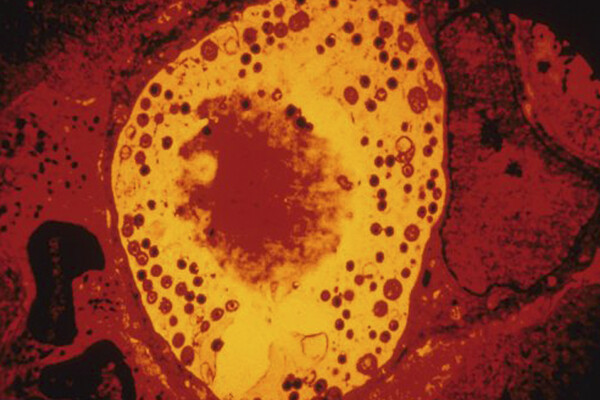

Анализ показал, что у пациентов с болезнью Альцгеймера в тканях сетчатки и головного мозга обнаруживались значительно более высокие концентрации хламидий. Это род грамотрицательных бактерий, виды которых относятся к облигатным внутриклеточным паразитам. Хламидии вызывают заболевания у человека, животных и птиц.

Чтобы разобраться в механизме, исследователи провели эксперименты на мышах. Они показали, что присутствие хламидий активирует хроническое воспаление, гибель нервных клеток и выработку бета-амилоида — токсичного для нейронов белка, накопление которого считается одной из центральных особенностей болезни Альцгеймера. В совокупности эти процессы ускоряли нейродегенерацию.